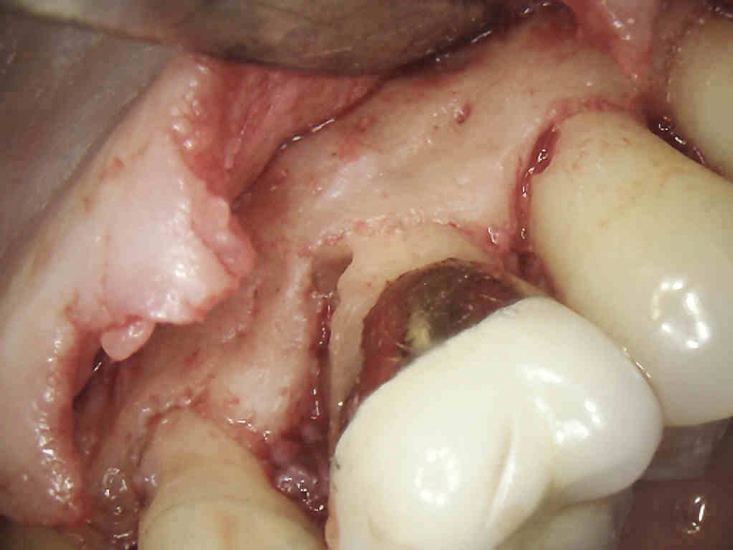

(7.) In cases in which an infrabony defect is inaccessible or surgical access would result in excessive removal of sound tooth structure, internal repair is the treatment of choice.

Figure 7

(8.) The defect is accessed through the pulp space and debrided with rotary or ultrasonic instruments.

Figure 8

(9.) The defect should be irrigated with saline as opposed to sodium hypochlorite because the portal allows for direct communication with the periodontal ligament space and a hypochlorite accident could occur.

Figure 9

(11.) The portal of entry is sealed with bioceramic materials, endodontic obturation is completed with gutta percha and sealer, and the tooth is restored.

Figure 11

(10.) A 90% TCA solution is applied using a paper point.

Figure 10